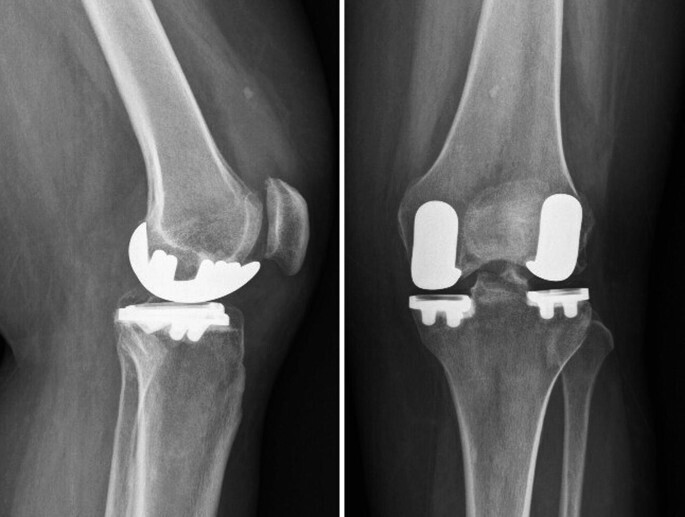

Conventional knee replacement surgery vs robotic knee replacement surgery Artofit How Much Is Knee Replacement Surgery Without Insurance How much is total knee replacement surgery with or without insurance? If a doctor has told you that you need a knee replacement, you probably have a lot of questions about what to expect. If you’re insured, you can usually expect to pay less for your procedure than an uninsured patient,. Meet knee surgeonsknee replacement surgery The average cost of. How Much Is Knee Replacement Surgery Without Insurance.